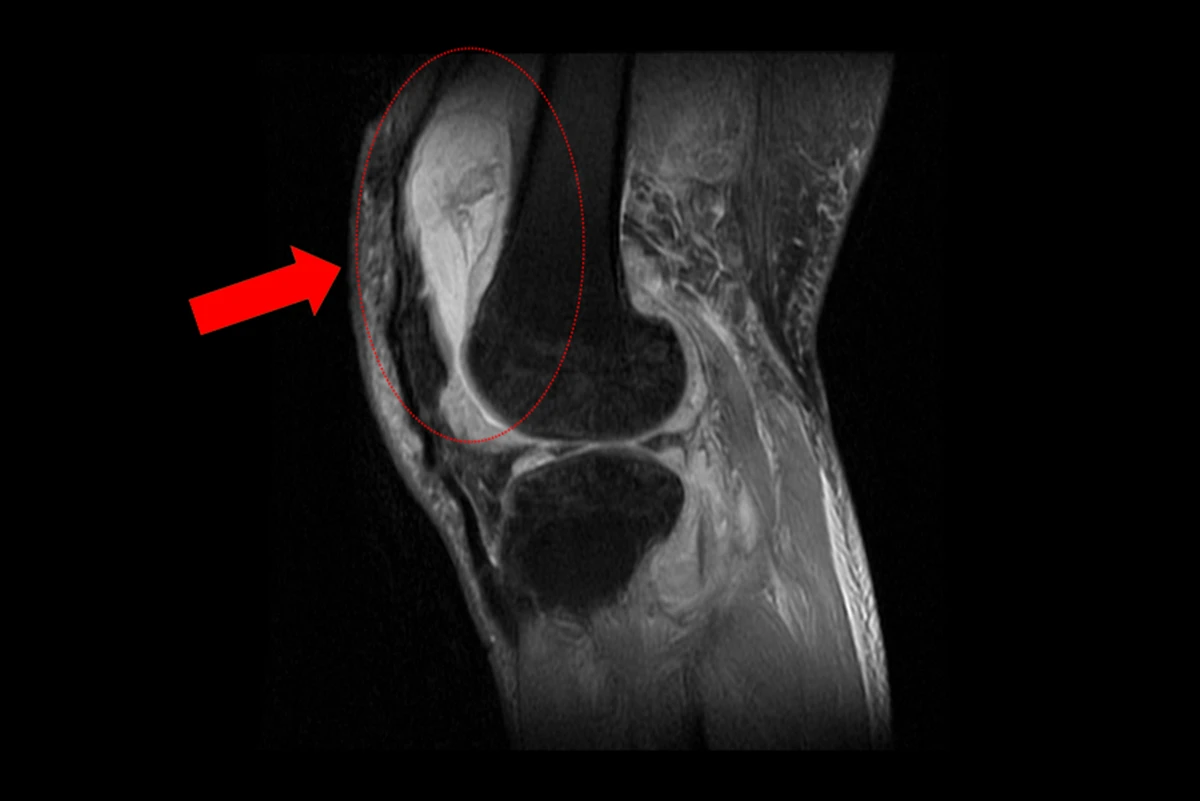

賴先生左膝長期腫痛,原以為是退化性關節炎,服用止痛藥、抽關節積水、熱敷復健數月卻越來越嚴重,來院時已腫到無法彎曲。關節液檢查顯示白血球偏高但不像一般細菌感染,因此安排住院做X光與核磁共振,結果發現膝內大量積膿,為嚴重關節感染。

為避免病人感染惡化,醫師緊急施行微創關節鏡清創手術,檢體送病理化驗後竟發現結核分枝桿菌,顯示並非單純膝蓋退化。後續會診感染科與胸腔科醫師共同診斷,在病人痰液培養出結核菌,證實為「肺結核合併肺外感染」。經抗結核治療1週後,膝蓋腫脹明顯改善,出院後仍需持續服藥至少9個月並定期追蹤,以確保結核完全清除。

X光顯示膝蓋內已有大量積液並化膿,屬於嚴重關節感染。(圖片來源:台中慈濟醫院)